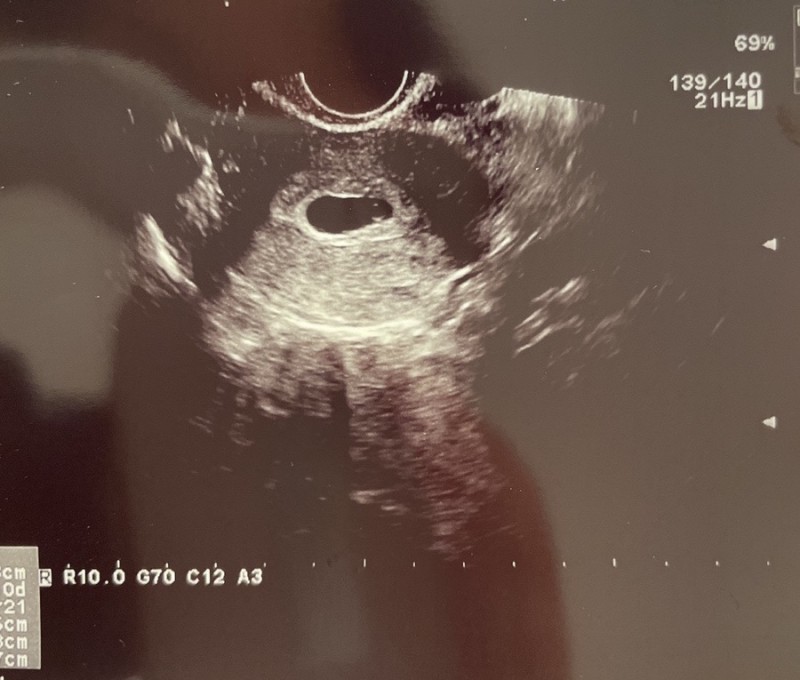

안녕?

5주 3일 째란다.

아기집과 난황크기 모두 좋다고 하셔서 마음이 한결 놓였다.

이날 임신확인서도 받고 다음주에는 아기심장 소리를 들을 수 있다고 했다.

하지만 피비침이 있어서 유산기가 있다고 하셔서

가슴이 철렁했다.

이날 절박유산 진단도 함께 받았다.

(절박유산 : 20주 이전 질 출혈이 동반되는 것을 말한다. 이는 임신 유지는 가능)